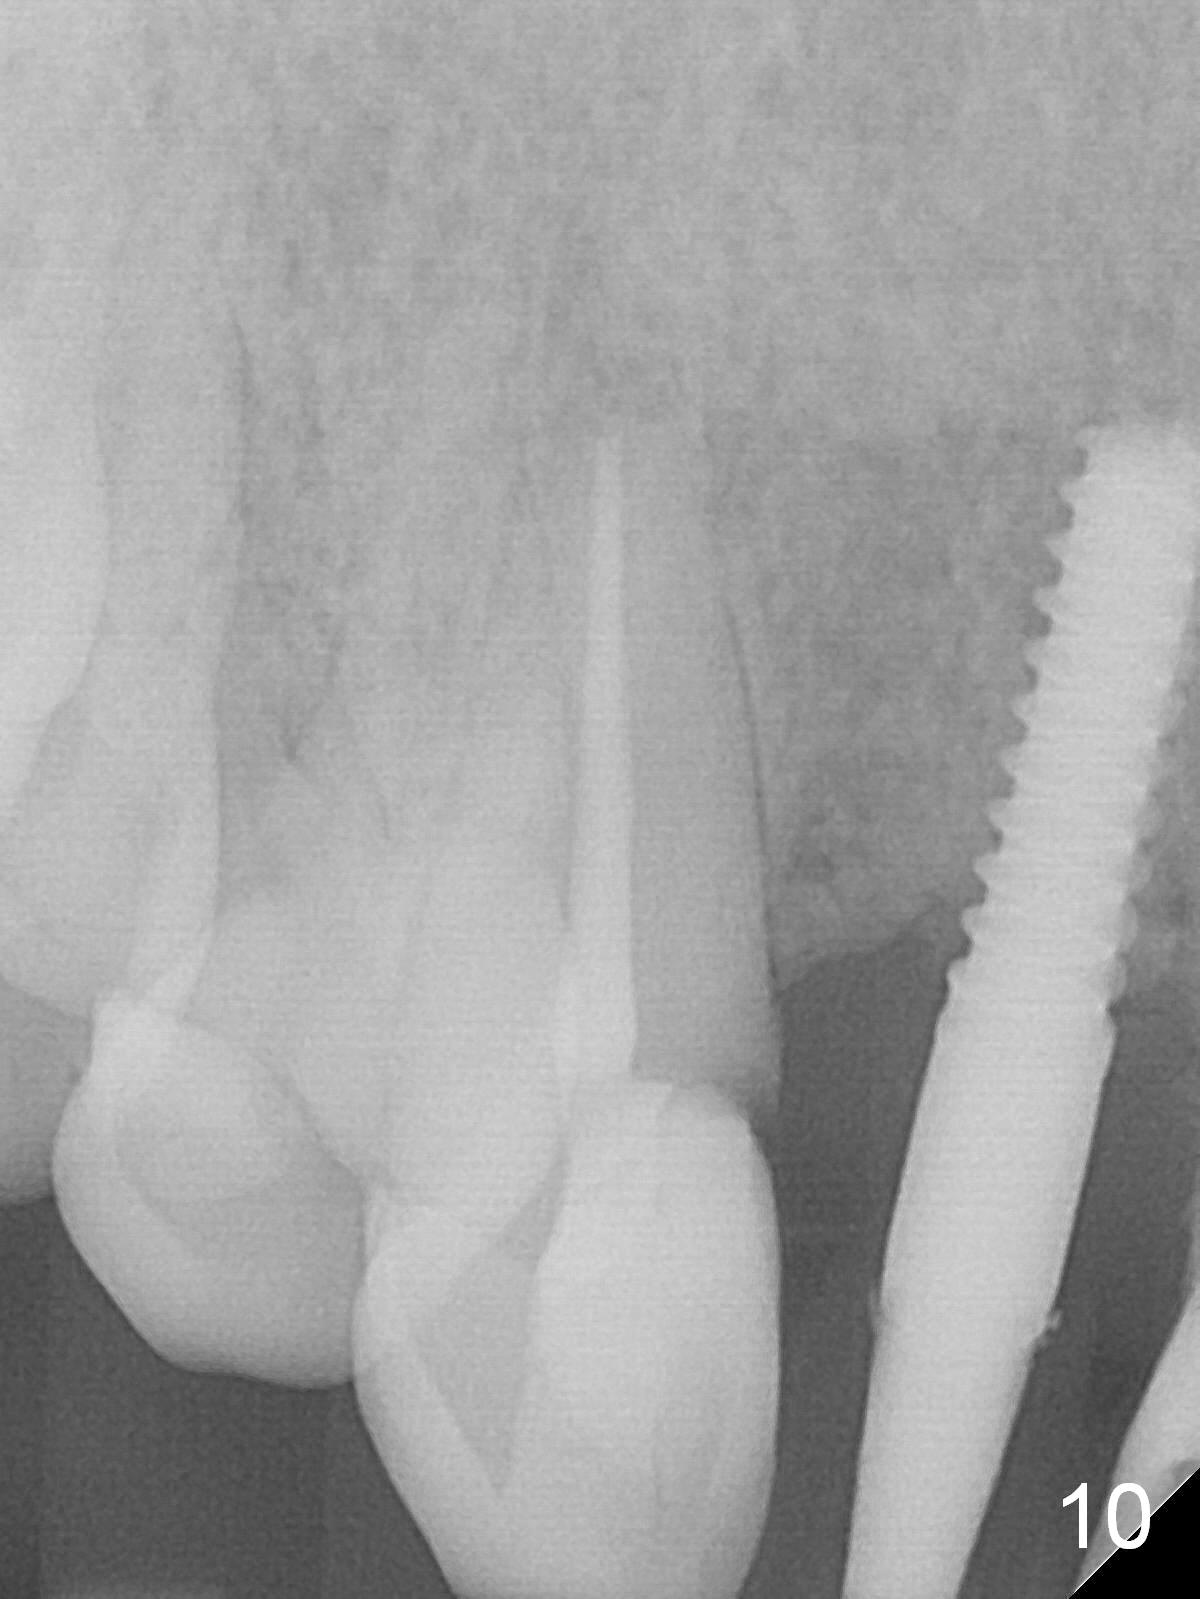

Extending the initial osteotomy to the full length of the implant is critical. If perforation is detected early, the trajectory can be changed. Incision should be made if there is no CBCT study. The incision heals 1 and 4 weeks postop (Fig.8,9). The patient returns for final restoration 6 months postop. Apical defects appear to have healed at #6 and 7 (Fig.10,11). Fig.12 is taken 11 months postop and 5 months post cementation. The patient has an accident 9 months post cementation. In fact the implant is alright, while the tooth #6 fractures and #8 subluxates.